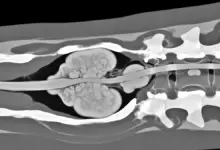

Escoliose é uma curvatura lateral da coluna que pode formar um “C” ou um “S” quando vista de frente.

Ela não é só “coluna torta”, porque a alteração também envolve rotação das vértebras, o que muda a forma do tronco.